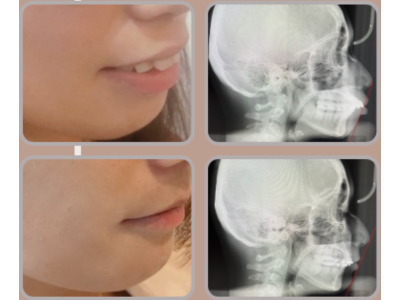

專業醫師,守護你的笑容 我們結合國際級植牙系統與數位美學技術,提供無痛、精準、快速的牙科治療體驗。從植牙、全瓷冠到隱形矯正,一次滿足你的需求。 預約諮詢 關於我們 精準重建每一個笑容 陳俊岳醫師率領的專業團隊,結合國際植牙技術與數位牙科系統,專精於微創植牙、全口重建、全瓷冠與隱形矯正。我們相信醫療不只是技術的展現,更是傾聽與信任的累積,讓每位患者都能安心重拾自然笑容。 醫師介紹 你所需要的牙科服務,一次到位 從植牙、全瓷美學到隱形矯正,為你提供最適合的解決方案 All-on-4 全口重建 透過四支植體即可支撐全口固定假牙,手術當天即可恢復咀嚼與笑容。省時、安全,是全口重建的高效新選擇。 微創植牙 結合 3D 導引技術與數位影像分析,僅需微小切口即可完成植牙。傷口小、恢復快,是患者首選的無痛精準植牙方式。 全瓷貼片 / 全瓷冠 高透光全瓷材質,重現自然笑容。從牙齒美白、縫隙修飾到整體微笑設計,打造專屬自信風采。 隱形矯正 透明舒適、可自行摘戴,結合數位3D掃描與模擬,讓矯正過程幾乎隱形,同時維持生活自信與美觀。 服務項目 想擁有更自信的笑容我們幫你實現! 不論是植牙、貼片還是矯正, 專業醫師團隊都會為你量身打造最自然的治療方案。 一次預約,即可完成影像健檢與療程規劃。立即體驗數位牙科的高效與舒適。 預約諮詢 選擇我們 精準醫療 × 美學設計 × 人本關懷 專業與溫度兼具的牙科團隊 陳俊岳醫師帶領的團隊結合國際植牙系統、數位牙科技術與多年的臨床經驗,為每位患者量身打造最適合的治療方案。我們堅持以人為本,讓治療更安全、美觀且長久穩定。 精準定位、傷口小、恢復快 客製化笑容美學設計 傾聽需求、尊重選擇,讓醫療更有溫度 診療案例 患者見證 他們的笑容,證明一切 「以前害怕看牙,來這裡完全改觀。醫師很有耐心,手法也很細膩, 植牙後完全沒有不適,現在咬東西都很自然。」 陳小姐・植牙治療 「我做了全瓷貼片,笑起來真的差好多! 醫師幫我設計的牙齒形狀超自然,朋友都以為是我原本的牙齒。」 林小姐・全瓷貼片美學修復 「我選擇做 All-on-4 全口重建,手術當天就能吃東西, 整個過程比想像中輕鬆很多,非常感謝團隊專業又溫柔的照顧。」 黃先生・全口重建 立即撥打 02-25533202 台北市大同區承德路二段176號 (捷運民權西路站2分鐘) 官方Line預約諮詢 台北院所 預約專線 02-25533202 台北市大同區承德路二段176號 (捷運民權西路站2分鐘) 台南院所 預約專線 06-3117111 台南市永康區中華二路189號 官方Line預約諮詢